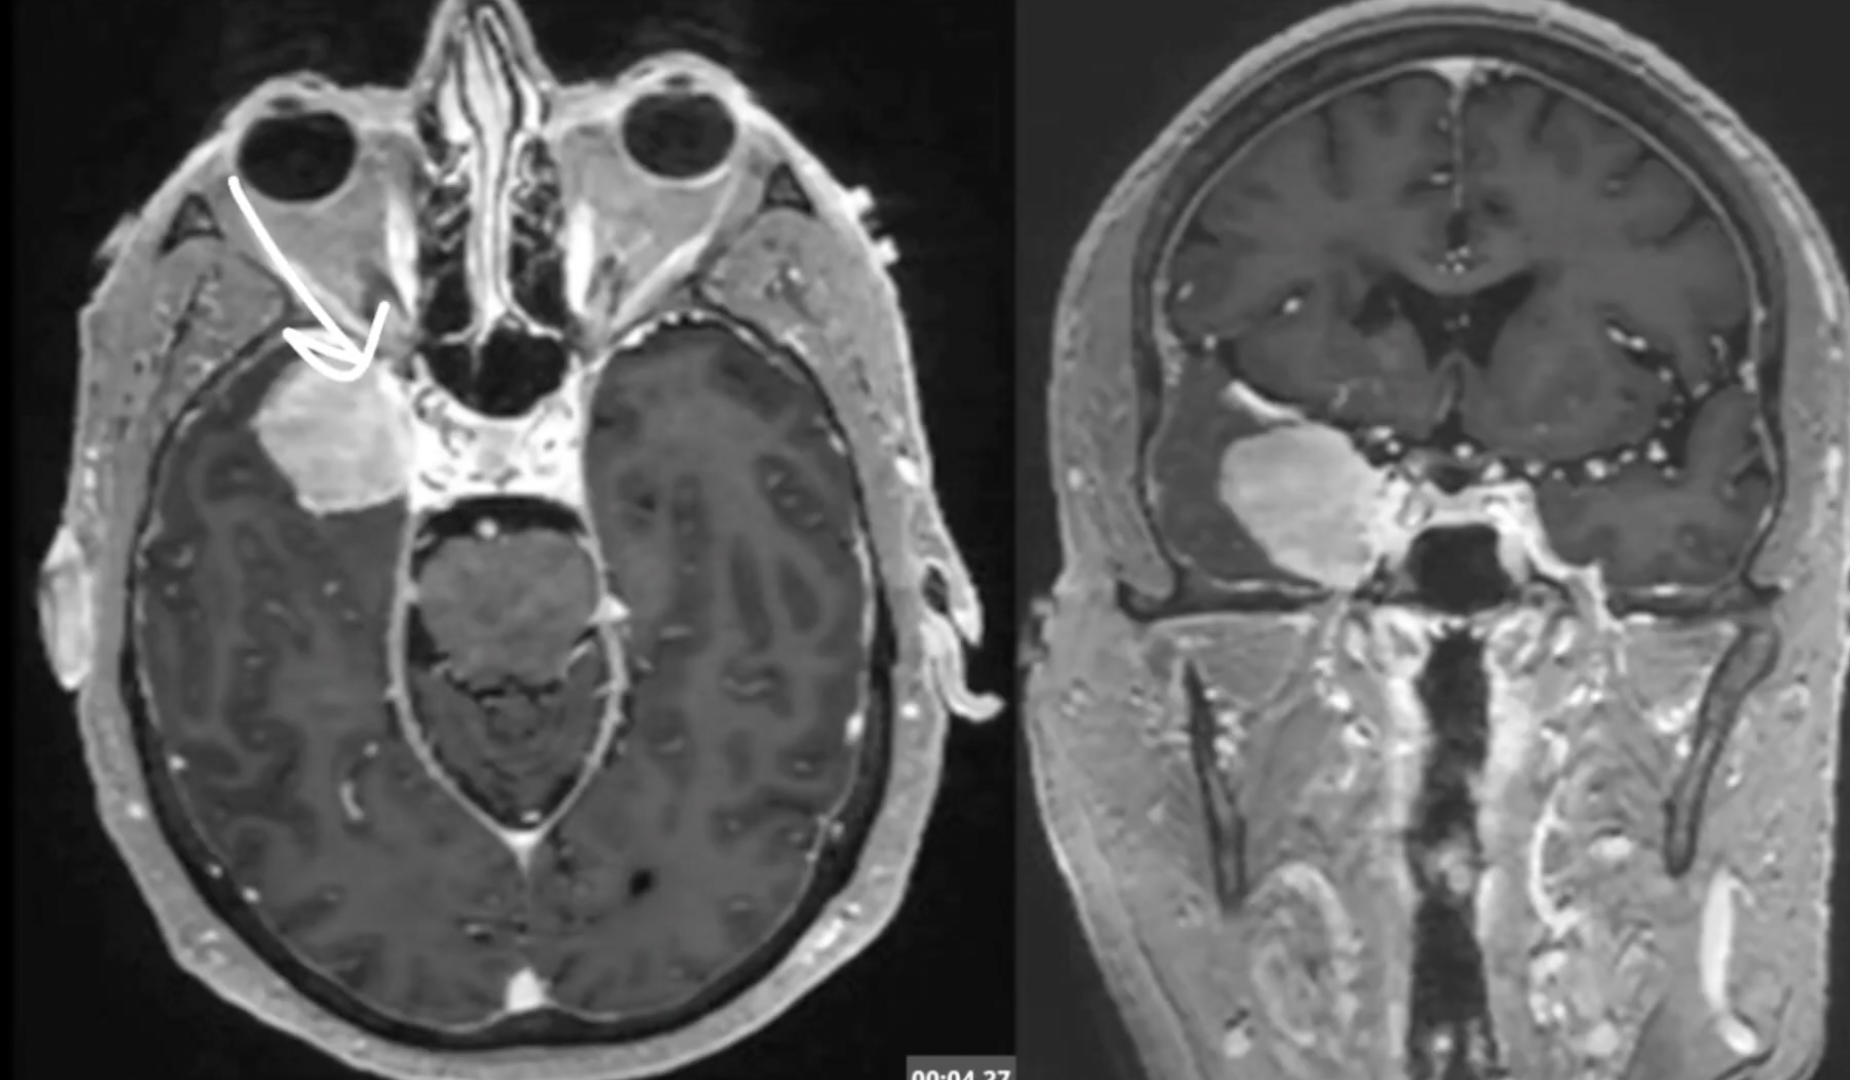

A purely endoscopic endonasal approach was used to remove suprasellar lesions in a series of 10 patients. Five lesions were prechiasmal (three tuberculum sellae and two planum sphenoidale meningiomas) and five were post-chiasmal (four craniopharyngiomas and one Rathke cleft cyst). The floor of the planum sphenoidale and the sella turcica was reconstructed using a multilayer closure with autologous and synthetic materials. Spinal drainage was performed in only five cases. Complete resection of the lesions was achieved in all but one patient. The pituitary stalk was preserved in all but one patient, whose stalk was invaded by a craniopharyngioma and who had preoperative diabetes insipidus (DI). Vision improved postoperatively in all patients with preoperative impairment. Six patients had temporary DI; in five, the DI became permanent. Four patients with craniopharyngiomas required cortisone and thyroid replacement. After a mean follow up of 10 months, there was only one transient CSF leak when a lumbar drain was clamped prematurely on postoperative Day 5.